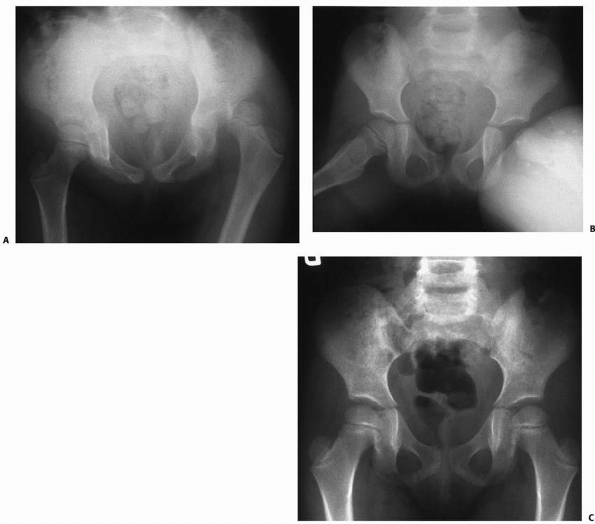

If a child suffers a fracture as a result of insignificant trauma, then

surgery,20 metabolic bone disease, or pathologic processes of the proximal femur (Fig. 21-1).

| FIGURE 21-1 A 10-year-old boy fractures through a unicameral bone cyst while running for a soccer ball. |